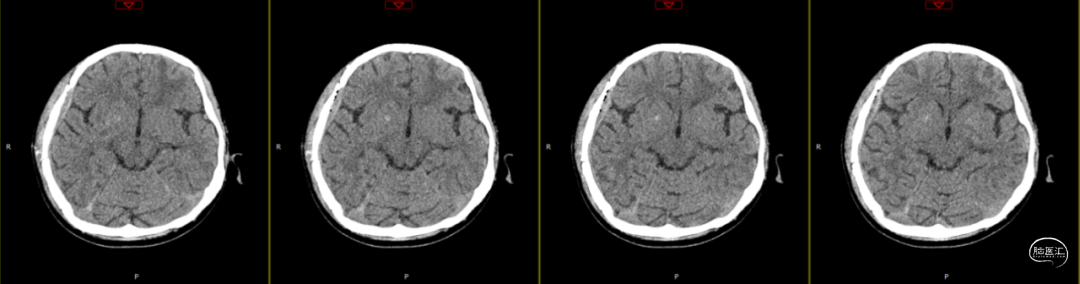

第3次术后第9天复查颅脑CT(如上图)。

第3次术后16天,复查颅脑MRI(如上图),硬膜外及皮下异常信号较前明显减少,负压引流管引流不明显,拔除负压引流管,继续使用头孢曲松+多西环素口服联合抗炎治疗。

第3次术后23天,拔管后7天复查颅脑(如上图)。

第3次手术后49天,出院后2周复查颅脑CT情况(如上图),刀口愈合正常,患者回归日常生活、学习。